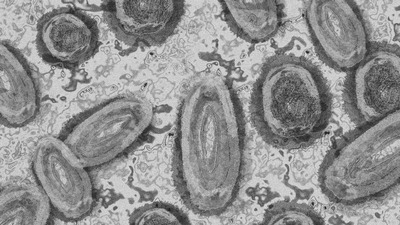

Haberler Sağlık Maymun çiçeği, Covid-19 ve HIV´in aynı anda bulunduğu vaka | Sağlık Haberleri

Hastaneye yatan ve vücudunda lezyonlar ortaya çıkan hastanın, 6 Temmuz´da maymun çiçeği, Covid ve HIV testleri sonucunda üç virüsünde vücudunda bulunduğu tespit edildi.

Catania ve Palermo Üniversitelerinden bilim insanları, şimdiye kadar bildirilen maymun çiçeği, Covid ve HIV'in aynı anda bulunduğu 'bilinen' tek vaka olduğunun altını çizdi.